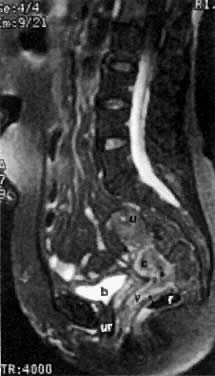

Fig. 15. Sagittal T2-weighted MRI of a stage IIA cervical carcinoma ( c) shows invasion in upper third of the posterior vaginal wall ( arrow ). ( u, uterus; v, vagina; b, bladder; r, rectum; ur, urethra.)